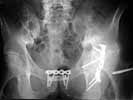

A male 53 years old Nov. 25, 2002 sustained multiple injuries including pelvic ring lesion, # of the left acetabulum, # of the right femoral shaft, left patella, also left ankle and right forearm. He was initially treated elsewhere on traction, the ankle in plastre cast and the forearm with ex-fix.

Referenced to us Mar. 25, 2003 - 4 months after the injury with healed femur, ankle and forearm. Pelvic external fixator was applied to correct the ring shape. Apr 28, 2003 the symphisys was plated and acetabular ORIF was performed mostly to prepare it for later THA.

So questions are - what to do with the left patella and quadriceps at the side of THA? Should axis and length of the opposite (right) femur be restored before? If not to touch the right femur, should the left femur be shortened during the THA?

3. Left THA can be done, but I wouldn't try to shorten very much at THA site because he's already short due to protrusio (compare levels of lesser trochanters to your reference of choice on the pelvis) and any significant shortening at hip may lead to poor abductor tension and attendant risk of dislocation (offset stem and liner options may allow correction for these).